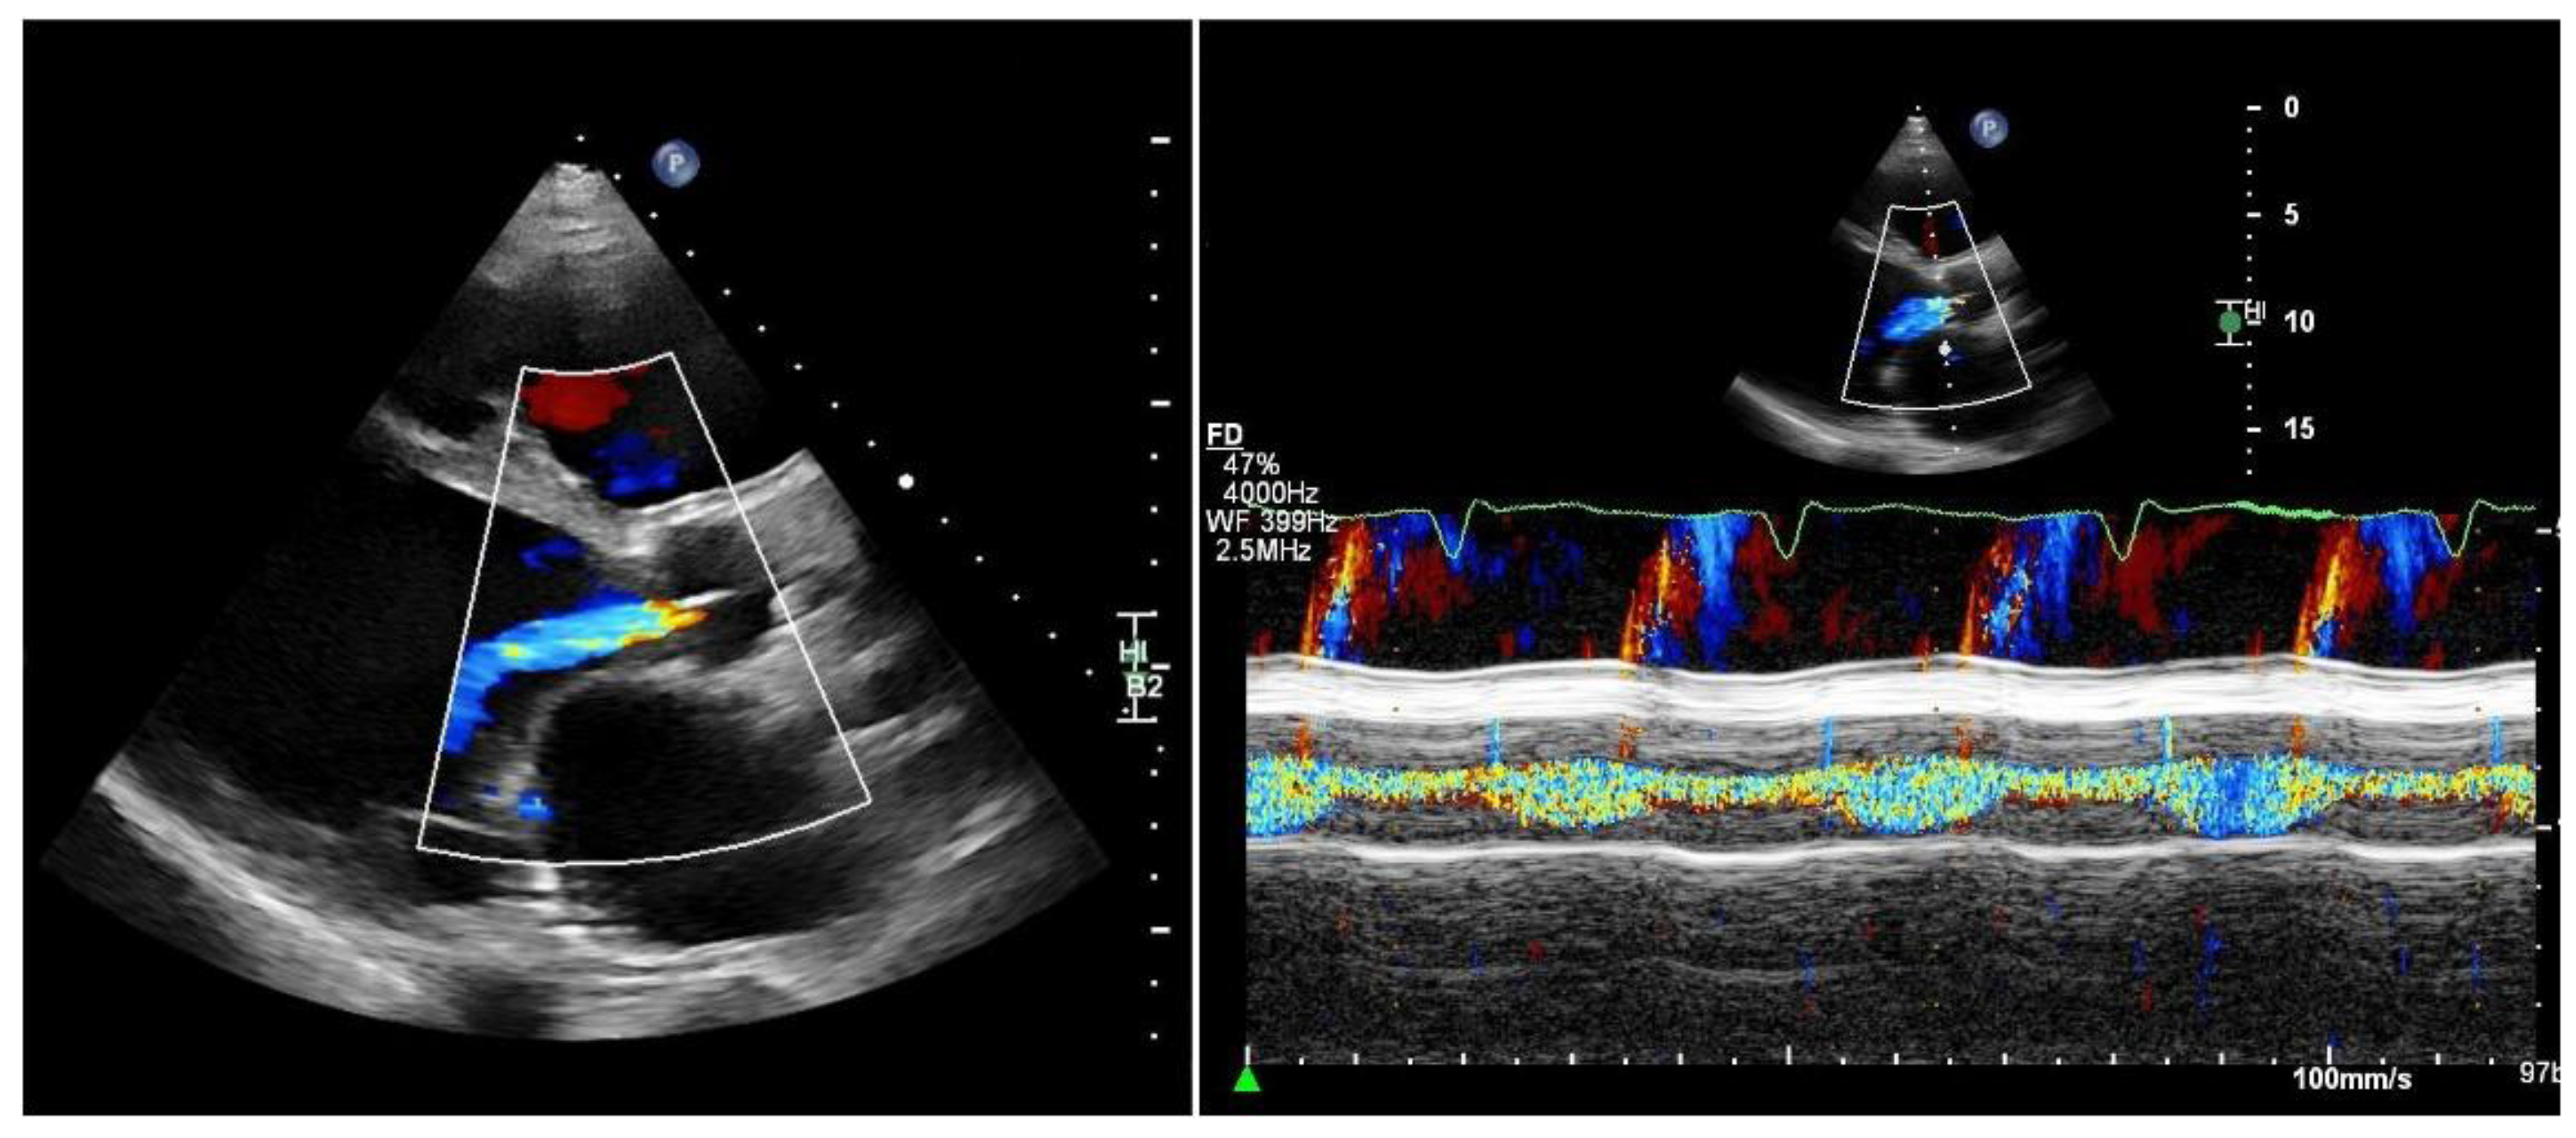

Quantifying aortic regurgitation (AR) in patients supported by a left ventricular assist device (LVAD) remains challenging. Conventional echocardiographic parameters are based on the assumption of isolated diastolic regurgitation, an assumption that often does not apply in the LVAD setting. In fact, holocyclic regurgitation (systolic and diastolic) is frequently observed, particularly in patients with more advanced AR (Figure 2).

Consequently, accurate quantification of AR should ideally be performed at specialized centers. Comprehensive assessment typically requires transthoracic echocardiography supplemented by transesophageal echocardiography to improve visualization of the regurgitant jet, as well as right heart catheterization for detailed hemodynamic evaluation [24,25].

As a practical and readily available approach, vena contracta width and the ratio of the regurgitant jet width to the left ventricular outflow tract (LVOT) diameter may be used for semi-quantitative assessment:

• Vena contracta width ≥ 3 mm

• Jet/LVOT ≥ 46% (compared with ≥ 60% in native aortic valves)

Both parameters suggest at least moderate, AR [27]. Conversely, if the regurgitant jet is absent or only mildly detectable during diastole, mild AR may be assumed. In addition, progressive left ventricular dilatation over time supports the presence of chronic volume overload and is consistent with hemodynamically significant AR, particularly in symptomatic patients.

Figure 2. Patient with an LVAD and significant aortic regurgitation. Left: parasternal long-axis view. Right: M-mode of the aortic valve. M-mode color Doppler imaging clearly demonstrates both systolic and diastolic regurgitation.